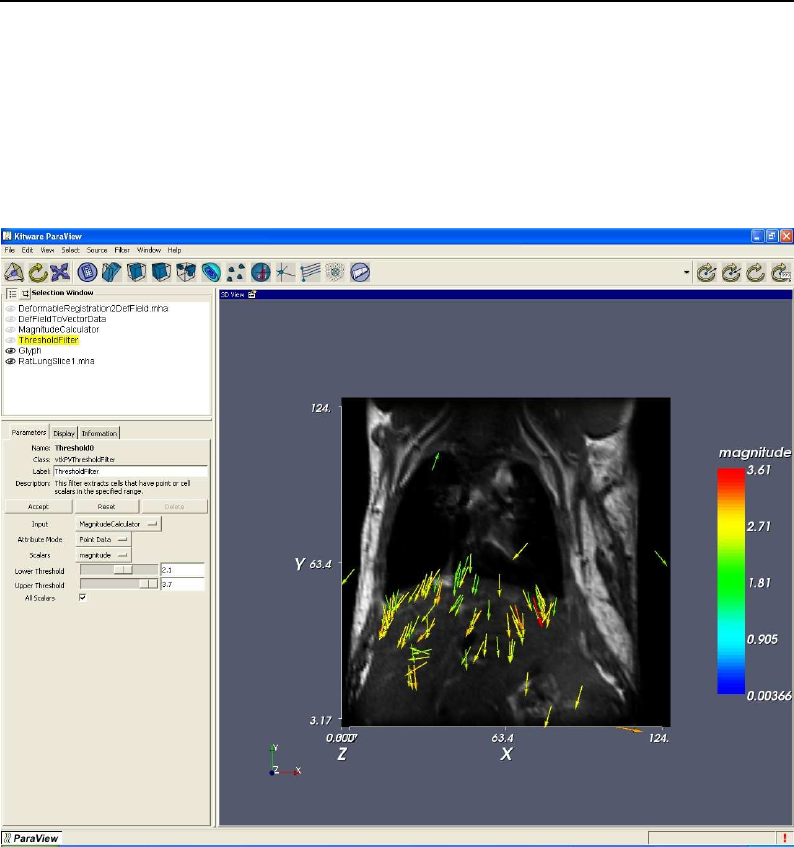

- Deformable Registration

- Demons Deformable Registration

- Visualizing Deformation fields